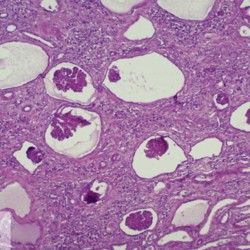

Etiquetes: B-590/92 3 total Canine Specie: Canine Organ: Kidney Lesion: Dysplasia Lesion modifier: - Disease: Juvenile nephropathy Files/Expedient: B-590/92 Not viewed Canine Specie: Canine Organ: Kidney Lesion: Dysplasia Lesion modifier: - Disease: Juvenile nephropathy Files/Expedient: B-590/92 Not viewed Canine Specie: Canine Organ: Kidney Lesion: Dysplasia Lesion modifier: - Disease: Juvenile nephropathy Files/Expedient: B-590/92 Not viewed Títol Select...Avian (Exotic) (110)Avian (Poultry) (76)Bovine (317)Canine (935)Caprine (47)Equine (257)Feline (326)Ferret (19)General (127)Marine mammal (22)Non-human primate (20)Ovine (328)Porcine (379)Rabbit (61)Reptile (38)Rodent (28)Wildlife (91) Format Select...- (60)Abomasum (37)Adrenal gland (10)Blood (7)Blood vessel (50)Body as a whole (19)Bone (57)Bone marrow (21)Brain (93)Cloaca (1)Diaphragm (2)Ear (5)Esophagus (39)Eye (16)Fetus (12)Gallbladder (23)Gizzard (2)Heart (265)Intestine (356)Joint (32)Kidney (443)Larynx (5)Liver (326)Lung (264)Lymph node (91)Mammary gland (10)Mediastinum (1)Muscle (22)Nasal cavity (22)Nerve (7)Omasum (5)Oral cavity (63)Ovary (14)Oviduct (8)Pancreas (7)Parathyroid (5)Penis (10)Peritoneum (65)Pharynx (9)Pituitary gland (6)Placenta (7)Prostate (8)Proventriculus (3)Reticulum (1)Rumen (28)Sinus (7)Skin (181)Spinal cord (15)Spleen (105)Stomach (125)Teeth (1)Testicle (11)Thoracic cavity (31)Thymus (13)Thyroid gland (5)Tongue (32)Tonsils (11)Trachea (11)Urethra (5)Urinay bladder (61)Uterus (27)Vagina (1)Vulva (1)Yolk sac (1) Cobertura Select...- (152)Abomasitis (26)Abscess (27)Acidosis (1)Adenocarcinoma (20)Adenoma (9)Aerosacculitis (6)Agenesis (1)Agnathia (1)Alopecia (7)Amyloidosis (12)Aneurysm (6)Angiectasis (1)Anthracosis (1)Arteritis (11)Arthritis (15)Arthrogryposis (6)Artifact (4)Ascites (13)Atelectasis (8)Atherosclerosis (5)Atresia (1)Atrial septal defect (2)Atrophy (10)Autolysis (7)Bronchitis (6)Bronchopneumonia (26)Cachexia (2)Carcinoma (103)Cardiomyopathy (19)Cellulitis (2)Chemodectoma (4)Cholangiohepatitis (4)Cholangitis (19)Cholecystitis (4)Cholestasis (5)Chondrodysplasia (2)Chondrosarcoma (2)Chronic passive congestion (13)Chylothorax (2)Cirrhosis (6)Coelomitis (3)Coenurus cerebralis (4)Colitis (40)Congestion (17)Conjunctivitis (5)Coronitis (3)Cryptorchidism (3)Cyst (25)Cystitis (24)Dermatitis (69)Diaphragmatic hernia (4)Dilation (28)Discospondylitis (1)Disseminated intravascular coagulation (7)Dyschondroplasia (1)Dysplasia (29)Ectopia cordis (1)Ectopic ureter (1)Edema (55)Emphysema (5)Encephalitis (5)Endocardiosis (14)Endocarditis (26)Endometritis (5)Enteritis (118)Enterolith (6)Epulis (3)Esophagitis (14)Fasciitis (1)Fibrosis (7)Fibrous osteodystrophy (8)Fistula (1)Folliculitis (3)Fracture (2)Gastritis (34)Gingivitis (5)Glioma (8)Glomerulonephritis (21)Glossitis (25)Glycogenosis (1)Gout (8)Granuloma (2)Granulosa cell tumor (4)Hemangioma (9)Hemangiosarcoma (46)Hematoma (8)Hemoglobinuria (2)Hemopericardium (12)Hemoperitoneum (2)Hemorrhage (100)Hemosiderosis (7)Hemothorax (2)Hepatitis (78)Hernia (11)Histiocytosis (3)Hydatid cyst (11)Hydrocephalus (9)Hydrometra (1)Hydronephrosis (22)Hydropericardium (6)Hydrothorax (3)Hydroureter (5)Hyperkeratosis (8)Hyperostosis (4)Hyperplasia (37)Hypertrophy (9)Hypopigmentation (1)Hypoplasia (7)Hypopyon (1)Impaction (6)Infarction (63)Insulinoma (6)Intussusception (5)Jaundice (17)Laminitis (2)Laryngitis (2)Leiomyoma (5)Leukemia (13)Lipidosis (36)Lipoma (7)Lymphadenitis (45)Lymphadenopathy (7)Lymphangiectasia (6)Lymphangitis (5)Lymphoma (221)Malacia (11)Malignant melanoma (15)Mast cell tumor (11)Mastitis (8)Megaesophagus (2)Melanosis (3)Melena (4)Meningioma (6)Meningitis (6)Meningocele (2)Meningoencephalitis (5)Mesothelioma (5)Methemoglobinemia (2)Mineralization (10)Mucocele (5)Mucometra (1)Multilobular bone tumor (1)Mummification (3)Myelofibrosis (1)Myocarditis (4)Myositis (5)Necrosis (81)Nephritis (113)Nephroblastoma (6)Nephrosclerosis (1)Nephrosis (14)Neuritis (1)Obstruction (13)Omasitis (4)Omphalitis (1)Omphalophlebitis (7)Orchitis (4)Osteoarthrosis (5)Osteomyelitis (9)Otitis (2)Palatoschisis (3)Pancreatitis (3)Panniculitis (3)Papilloma (7)Parakeratosis (14)Patent ductus arteriosus (6)Peliosis hepatis (1)Perforation (17)Pericarditis (35)Peritonitis (39)Persistent right aortic arch (1)Pharyngitis (2)Pheochromocytoma (2)Phlebitis (2)Placentitis (6)Pleuritis (21)Pleuropneumonia (24)Pneumonia (109)Pneumothorax (3)Polycystosis (14)Polyp (5)Polyserositis (6)Posthitis (1)Proctitis (4)Prolapse (3)Prostatitis (3)Proventriculitis (1)Pyelonephritis (24)Pyometra (6)Pyothorax (4)Rhinitis (11)Rumenitis (6)Rupture (24)Salpingitis (3)Sarcoma (57)Sclerosis (1)Scoliosis (2)Seminoma (2)Sequestrum (2)Serous atrophy (14)Sinusitis (7)Splenitis (14)Splenomegaly (9)Spondylitis (6)Spondylosis (1)Stenosis (9)Stomatitis (32)Tenosynovitis (2)Teratoma (3)Thricobezoar (2)Thrombosis (16)Tonsilitis (4)Torsion (13)Tracheitis (4)Tympany (7)Typhlitis (8)Typhlocolitis (4)Ulcer (43)Urethritis (1)Urolithiasis (36)Uroperitoneum (1)Uveitis (1)Vasculitis (15)Ventricular septal defect (3)Volvulus (11) Matèria Select... - (14)- (1653)- (152)Abomasitis - Catarrhal (2)Abomasitis - Catarrhal-hemorrhagic (1)Abomasitis - Chronic (1)Abomasitis - Fibrinous-necrotizing (2)Abomasitis - Hyperplasic (5)Abomasitis - Hyperplasic - Chronic (1)Abomasitis - Necrotic (1)Abomasitis - Necrotizing (2)Abomasitis - Ulcerative (5)Adenocarcinoma (9)Aerosacculitis - Granulomatous (1)Amyloidosis - Chronic (1)Arteritis - Necrotic (2)Arteritis - Necrotizing (1)Arthritis - Chronic (4)Arthritis - Fibrinous-purulent (3)Arthritis - Serous (4)Arthritis - Subacute (1)Ascites - Serous (1)Atrophy - Serous (1)Bronchitis - Catarrhal (3)Bronchitis - Suppurative (1)Bronchopneumonia - Catarrhal-purulent (17)Bronchopneumonia - Fibrinous (1)Bronchopneumonia - Granulomatous (1)Bronchopneumonia - Purulent (1)Bronchopneumonia - Suppurative (5)Carcinoma - Adenocarcinoma (33)Carcinoma - Adenocarcinoma - Hepatocellular (2)Carcinoma - Adenocarcinoma - Mucinous (1)Carcinoma - Basosquamous (1)Carcinoma - Cholangiocellular (3)Carcinoma - Hepatocellular (4)Carcinoma - Metastatic (3)Carcinoma - Squamous cell carcinoma (13)Carcinoma - Transitional cell (2)Cardiomyopathy - Dilated (13)Cardiomyopathy - Hypertrophic (6)Cellulitis - Necrotizing (1)Cholangitis - Chronic (8)Cholangitis - Hyperplasic (3)Cholecystitis - Fibrinous-necrotizing (1)Coelomitis - Fibrinous (1)Coelomitis - Granulomatous (1)Colitis - Catarrhal (3)Colitis - Catarrhal-hemorrhagic (1)Colitis - Fibrinous (1)Colitis - Fibrinous-necrotizing (1)Colitis - Fibrinous-necrotizing (Diphtheritic) (6)Colitis - Granulomatous (2)Colitis - Hemorrhagic (4)Colitis - Hemorrhagic-necrotizing (3)Colitis - Necrotizing (2)Colitis - Ulcerative (6)Congestion - Chronic (2)Conjunctivitis - Hyperplasic (1)Conjunctivitis - Purulent (3)Coronitis - Ulcerative (1)Cystitis - Chronic (3)Cystitis - Fibrinous (1)Cystitis - Fibrinous-necrotizing (1)Cystitis - Follicular (1)Cystitis - Hemorrhagic (6)Cystitis - Hemorrhagic-ulcerative (1)Cystitis - Necrotizing (9)Cystitis - Perforated (1)Dermatitis - Granulomatous (14)Dermatitis - Hyperkeratotic (10)Dermatitis - Hyperplasic (proliferative) (1)Dermatitis - Hyperplastic (10)Dermatitis - Necrotizing (4)Dermatitis - Pustular (4)Dermatitis - Ulcerative (2)Dilation - Chronic (1)Discospondylitis - Necrotizing (1)Dysplasia - Follicular (5)Edema - Interstitial (6)Emphysema - Interstitial (1)Encephalitis - Granulomatous (1)Encephalitis - Nonsuppurative (1)Endocardiosis - Mitral (7)Endocardiosis - Mitral - Chronic (5)Endocarditis - Valvular (6)Endocarditis - Valvular - Mitral (7)Endocarditis - Valvular - Pulmonic (1)Endocarditis - Valvular - Subacute (1)Endocarditis - Valvular - Subaortic (5)Endocarditis - Valvular - Tricuspid (4)Endometritis - Purulent (3)Endometritis - Purulent-hemorrhagic (2)Enteritis - Catarrhal (23)Enteritis - Catarrhal - Acute (1)Enteritis - Catarrhal-hemorrhagic (5)Enteritis - Catarrhal-hemorrhagic - Acute (2)Enteritis - Fibrinous (16)Enteritis - Fibrinous - Acute (3)Enteritis - Fibrinous-necrotizing (7)Enteritis - Granulomatous (14)Enteritis - Granulomatous - Chronic (1)Enteritis - Granulomatous - Multifocal (1)Enteritis - Hemorrhagic (17)Enteritis - Hemorrhagic - Acute (1)Enteritis - Hemorrhagic-necrotizing (1)Enteritis - Hyperplasic (proliferative) (4)Enteritis - Necrotizing (4)Enteritis - Necrotizing - Acute (1)Enteritis - Necrotizing - Hemorrhagic (1)Enteritis - Necrotizing-ulcerative (2)Enteritis - Ulcerative (1)Enteritis - Ulcerative-hemorrhagic (1)Esophagitis - Erosive-ulcerative (6)Esophagitis - Necrotizing (4)Esophagitis - Ulcerative (1)Esophagitis - Ulcerative-necrotizing (1)Fasciitis - Fibrinous-purulent (1)Folliculitis - Purulent (2)Gastritis - Catarrhal (2)Gastritis - Chronic (1)Gastritis - Follicular (1)Gastritis - Hemorrhagic (2)Gastritis - Hemorrhagic-necrotizing (1)Gastritis - Hypertrophic (2)Gastritis - Inclusion bodies (1)Gastritis - Mineralization (1)Gastritis - Mycotic (1)Gastritis - Necrotizing (2)Gastritis - Ulcerative (6)Gastritis - Uremic (3)Gingivitis - Erosive (2)Gingivitis - Hyperplasic (proliferative) (1)Gingivitis - Necrotizing (1)Glomerulonephritis - Chronic (7)Glomerulonephritis - Membranoproliferative (3)Glomerulonephritis - Membranoproliferative - Chronic (1)Glomerulonephritis - Membranous (3)Glomerulonephritis - Membranous - Chronic (1)Glomerulonephritis - Proliferative (2)Glomerulonephritis - Subacute (1)Glossitis - Erosive (2)Glossitis - Granulomatous (6)Glossitis - Hyperplasic (1)Glossitis - Hyperplasic (proliferative) (2)Glossitis - Hyperplastic (1)Glossitis - Necrotizing (2)Glossitis - Necrotizing - Focal (1)Glossitis - Ulcerative (6)Glossitis - Ulcerative - Multifocal (1)Glossitis - Ulcerative - Subacute (1)Glycogenosis (1)Granuloma - Eosinophilic (1)Hemangiosarcoma - Metastatic (2)Hemorrhage - Acute (1)Hemorrhage - Subcapsular (3)Hepatitis - Abscess (9)Hepatitis - Acute (3)Hepatitis - Chronic (4)Hepatitis - Chronic interstitial (6)Hepatitis - Granulomatous (7)Hepatitis - Interstitial - Multifocal (1)Hepatitis - Interstitial - Subacute (1)Hepatitis - Necrotizing (17)Hepatitis - Necrotizing - Acute (2)Hepatitis - Necrotizing - Hemorrhagic (1)Hepatitis - Necrotizing - Subacute (1)Hepatitis - Pyogranulomatous (7)Hepatitis - Subacute (4)Hydronephrosis - Chronic (1)Hydropericardium - Chronic (1)Hyperplasia - Erythroid (1)Hyperplasia - Lymphoid (3)Hyperplasia - Myeloid (1)Hyperplasia - Nodular (8)Hypertrophy - Concentric (2)Hypertrophy - Eccentric (3)Infarction - Acute (17)Infarction - Acute - Multifocal (2)Infarction - Chronic (5)Infarction - Chronic - Multifocal (1)Infarction - Subacute (18)Infarction - Subacute - Focal (2)Laminitis - Chronic (2)Laryngitis - Necrotic (1)Laryngitis - Necrotizing (1)Leukemia - Lymphoid leukemia (2)Leukemia - Non-lymphoid leukemia (6)Lipidosis - Multifocal (1)Lipidosis - Panlobular (1)Lipidosis - Panlobular - Generalized (2)Lymphadenitis - Granulomatous (24)Lymphadenitis - Granulomatous - Chronic (3)Lymphadenitis - Hemorrhagic (1)Lymphadenitis - Necrotizing (5)Lymphadenitis - Necrotizing (caseous) (11)Lymphangitis - Granulomatous (1)Lymphangitis - Purulent (1)Lymphangitis - Ulcerative (1)Lymphoma - Alimentary lymphoma (7)Lymphoma - Cutaneous lymphoma (6)Lymphoma - Lymphosarcoma (2)Lymphoma - Mediastinal lymphoma (1)Lymphoma - Multicentric lymphoma (29)Malignant melanoma - Malignant (1)Malignant melanoma - Metastatic (1)Mast cell tumor - Metastatic (1)Mastitis - Fibrinous-purulent (2)Mastitis - Necrotic (1)Mastitis - Purulent (3)Mastitis - Suppurative (1)Meningitis - Fibrinous-purulent (2)Meningitis - Purulent (4)Meningoencephalitis - Necrotizing (3)Meningoencephalitis - Nonsuppurative (2)Mineralization - Metastatic (4)Myocarditis - Fibrous - Chronic (1)Myocarditis - Granulomatous (1)Myositis - Purulent (2)Necrosis - Acute (1)Necrosis - Cortical (5)Necrosis - Follicular (1)Necrosis - Papillary (8)Necrosis - Papillary - Acute (3)Necrosis - Subacute (3)Necrosis - Tubular (6)Nephritis - Embolic (2)Nephritis - Embolic suppurative (7)Nephritis - Granulomatous (27)Nephritis - Granulomatous - Chronic (1)Nephritis - Granulomatous - Multifocal (1)Nephritis - Interstitial (6)Nephritis - Interstitial - Acute (4)Nephritis - Interstitial - Chronic (41)Nephritis - Interstitial - Subacute (12)Nephritis - Purulent (7)Nephritis - Purulent - Acute (2)Nephritis - Purulent - Multifocal (3)Nephrosis - Cholemic (3)Nephrosis - Hemoglobinuric (10)Omasitis - Fibrinous-necrotizing (1)Omasitis - Hyperkeratotic (1)Omasitis - Necrotizing (2)Omphalophlebitis - Fibrinous-purulent (2)Omphalophlebitis - Purulent (3)Orchitis - Necrotizing (1)Osteomyelitis - Necrotizing (7)Osteomyelitis - Purulent (2)Otitis - Necrotizing (1)Otitis - Proliferative (1)Pancreatitis - Acute (1)Pancreatitis - Chronic (1)Pancreatitis - Granulomatous (1)Panniculitis - Fibrinous-purulent (1)Panniculitis - Necrotic (1)Panniculitis - Parasitic (1)Perforation - Acute (2)Pericarditis - Fibrinous (19)Pericarditis - Fibrinous - Subacute (1)Pericarditis - Fibrinous-necrotizing (1)Pericarditis - Fibrinous-purulent (3)Pericarditis - Fibrous (1)Pericarditis - Fibrous - Chronic (1)Pericarditis - Gangrenous (6)Pericarditis - Granulomatous (1)Pericarditis - Granulomatous - Chronic (2)Peritonitis - Acute (1)Peritonitis - Fibrinous (11)Peritonitis - Fibrinous - Subacute (1)Peritonitis - Fibrinous-purulent (5)Peritonitis - Fibrous (3)Peritonitis - Granulomatous (6)Peritonitis - Purulent (1)Peritonitis - Purulent-hemorrhagic (1)Peritonitis - Pyogranulomatous (3)Pharyngitis - Fibrinous-necrotizing (1)Pharyngitis - Ulcerative (1)Pheochromocytoma - Metastatic (1)Phlebitis - Purulent (1)Placentitis - Fibrinous-necrotizing (1)Placentitis - Necrotic (1)Placentitis - Necrotizing (1)Pleuritis - Chronic (1)Pleuritis - Fibrinous (3)Pleuritis - Fibrinous-purulent (2)Pleuritis - Fibrous (2)Pleuritis - Granulomatous (3)Pleuritis - Hyperplastic (2)Pleuritis - Purulent (2)Pleuritis - Pyogranulomatous (1)Pleuropneumonia - Fibrinous (13)Pleuropneumonia - Fibrinous-necrotizing (5)Pleuropneumonia - Granulomatous (2)Pleuropneumonia - Hemorrhagic-necrotizing (4)Pneumonia - Aspiration (11)Pneumonia - Bronchointerstitial (4)Pneumonia - Bronchointerstitial - Subacute (1)Pneumonia - Embolic (5)Pneumonia - Granulomatous (37)Pneumonia - Granulomatous - Multifocal (4)Pneumonia - Hemorrhagic-necrotizing (2)Pneumonia - Interstitial (7)Pneumonia - Interstitial - Acute (8)Pneumonia - Interstitial - Chronic (6)Pneumonia - Interstitial - Subacute (15)Pneumonia - Necrotizing (2)Pneumonia - Pyogranulomatous (2)Pneumonia - Verminous (5)Polyserositis - Fibrinous (6)Polyserositis - Fibrous (1)Proctitis - Fibrinous-necrotizing (1)Proctitis - Parasitic (2)Prostatitis - Purulent (1)Pyelonephritis - Acute (2)Pyelonephritis - Chronic (3)Rhinitis - Catarrhal (2)Rhinitis - Fibrinous (1)Rhinitis - Granulomatous (4)Rhinitis - Purulent (3)Rumenitis - Acute (1)Rumenitis - Erosive (1)Rumenitis - Necrotizing (1)Rupture - Acute (3)Sarcoma - Fibrosarcoma (12)Sarcoma - Hemangiosarcoma (11)Sarcoma - Histiocytic (7)Sarcoma - Metastatic (1)Sarcoma - Multilobular tumor of bone (1)Sequestrum - Chronic (2)Sinusitis - Suppurative (1)Splenitis - Granulomatous (8)Splenitis - Granulomatous - Chronic (1)Splenitis - Necrotizing (3)Splenitis - Necrotizing (caseous) (2)Spondylitis - Necrotizing (2)Stenosis - Intestinal (1)Stenosis - Valvular - Subaortic (4)Stomatitis - Erosive (12)Stomatitis - Erosive-ulcerative (3)Stomatitis - Fibrinous-necrotizing (1)Stomatitis - Fibrinous-necrotizing (Diphtheritic) (1)Stomatitis - Granulomatous (1)Stomatitis - Hyperplasic (1)Stomatitis - Hyperplasic (proliferative) (1)Stomatitis - Necrotizing (2)Stomatitis - Ulcerative (5)Stomatitis - Ulcerative - Multifocal (1)Stomatitis - Ulcerative-necrotizing (1)Tonsilitis - Necrotizing (4)Torsion - Acute passive hyperemia (5)Tracheitis - Catarrhal (3)Tracheitis - Fibrinous (1)Tracheitis - Granulomatous (1)Typhlitis - Catarrhal (1)Typhlitis - Fibrinous-necrotizing (2)Typhlitis - Hemorrhagic (2)Typhlitis - Ulcerative-hemorrhagic (1)Typhlocolitis - Fibrinous-necrotizing (2)Typhlocolitis - Proliferative (1)Ulcer - Chronic (6)Ulcer - Multifocal (2)Ulcer - Mycotic (1)Ulcer - Perforated (6)Urethritis - Hemorrhagic (1)Urolithiasis - Chronic (2)Uveitis - Granulomatous (1)Vasculitis - Granulomatous (1)Vasculitis - Necrotizing (1) Editor Select...- (1970)Acidosis (2)Actinobacillosis (Pleuropneumonia) (11)Aelurostrongylosis (2)African horse sickness (13)African swine fever (14)Alopecia X (1)Anaplasmosis (4)Anthrax (2)Aortic thromboembolism (feline) (7)Ascariasis (15)Aspergillosis (18)Atopic dermatitis (1)Atrophic rhinitis (3)Babesiosis (6)Blackhead (1)Bluetongue (11)Border disease (2)Bovine viral diarrhea (21)Brucellosis (2)Candidiasis (5)Canine distemper (14)Caprine arthritis-encephalitis (2)Capture myopathy (1)Cardiac insufficiency (17)Caseous lymphadenitis (7)Chlamydiosis (2)Classical swine fever (19)Clostridiosis (19)Coccidiosis (9)Coenurosis (4)Colibacillosis (21)Contagious ecthyma (7)Copper toxicosis (11)Cowdriosis (Heartwater) (3)Cryptococcosis (3)Cryptosporidiosis (2)Cysticercosis (23)Demodicosis (1)Diabetes (1)Dicrocoeliosis (5)Dictyocaulosis (4)Dirofilariasis (7)Discoid lupus erythematosus (3)Echinococcosis (17)Edema disease (7)Egg drop syndrome (1)Encephalitozoonosis (5)Enterotoxemia (1)Enzootic bovine leukosis (46)Epitheliogenesis imperfecta (3)Equine rhinopneumonitis (2)Equine verminous arteritis (strongylosis) (7)Erysipelas (5)Exudative epidermitis (7)Fasciolasis (11)Feline eosinophilic dermatoses (1)Feline hepatic lipidosis (8)Feline histiocytosis (4)Feline infectious peritonitis (38)Feline leukemia (4)Feline lower urinary tract disease (3)Feline panleukopenia (16)Feline viral rhinotracheitis (1)Flea allergy dermatitis (1)Foot and mouth disease (2)Gasterophilosis (4)Glasser's disease (15)Gousiekte (4)Gout (6)Haemonchosis (9)Hemolytic anemia (4)Hemorrhagic diathesis (1)Hepatic insufficiency (11)Hepatosis dietetica (7)Herpesvirosis (6)Hyperadrenocorticism (7)Hyperparathyroidism (10)Hypertrophic osteopathy (6)Hypervitaminosis D (1)Hypodermosis (1)Inclusion body hepatitis (4)Infectious bovine rhinotracheitis (5)Infectious bronchitis (5)Infectious canine hepatitis (13)Influenza (4)Juvenile nephropathy (8)Lamb dysentery (4)Leishmaniasis (28)Leptospirosis (1)Leukosis (5)Listeriosis (4)Lumpy skin disease (3)Maedi-visna (4)Malignant catarrhal fever (12)Mange (6)Mannheimiosis (5)Marek's disease (7)Metabolic bone disease (2)Mucoid enteropathy (5)Mulberry heart disease (5)Myasis (1)Mycobacteriosis (22)Mycosis fungoides (6)Myxomatosis (3)Necrobacillosis (5)Neonatal isoerythrolysis (6)Nocardiosis (4)Oestrosis (2)Onchocerciasis (1)Osteochondrosis (1)Ostertagiosis (6)Ovine pulmonary adenocarcinoma (5)Oxyuriasis (1)Pacheco's disease (4)Papillomatosis (6)Paratuberculosis (18)Parvovirosis (17)Pasteurellosis (11)Pemphigus foliaceus (1)Periodontal disease (1)Polioencephalomalacia of ruminants (4)Polyarteritis nodosa (3)Polycystic kidney disease (13)Porcine circovirosis (11)Porcine dermatitis and nephropathy syndrome (9)Porcine proliferative enteropathy (4)Porcine reproductive and respiratory syndrome (6)Porcine stress syndrome (1)Pox (13)Pregnancy toxemia (3)Proventricular dilatation disease (2)Pseudotuberculosis (yersiniosis) (2)Psittacine beak and feather disease (PBFD) (5)Pyoderma (4)Q fever (4)Rabbit hemorrhagic disease (2)Renal insufficiency (12)Reticuloendotheliosis (2)Rhodococcosis (1)Rickets (1)Rinderpest (2)Salmonellosis (34)Sarcosporidiosis (2)Schmallenberg (7)Septicemia (23)Spirocercosis (11)Streptococcosis (5)Strongylosis (1)Swine dysentery (5)Systemic coronavirosis (5)Tetralogy of Fallot (5)Theileriosis (13)Thromboembolism (5)Toxoplasmosis (11)Transmissible viral proventriculitis (1)Traumatic reticuloperitonitis (3)Traumatism (16)Tuberculosis (58)Ulcerative lymphangitis (1)Uremic syndrome (20)Viral arthritis (6)White muscle disease (9)Wobbler syndrome (2)Xanthomatosis (1)Zygomycosis (4) Idioma Select...- (1180)Bacterial (501)Degeneration (106)Fungal (46)Hemodynamic (112)Idiopathic (22)Inflammation (58)Malformation (88)Neoplasia (343)Nutritional (41)Parasitic (243)Physical/Chemical (93)Toxic (44)Viral (304) Ítem destacat Canine Acanthomatous ameloblastoma (acanthomatous epuli). Note tooth deviation consequence of invasion of local alveolar bone. Courtesy of Dr. Silvia Moreno